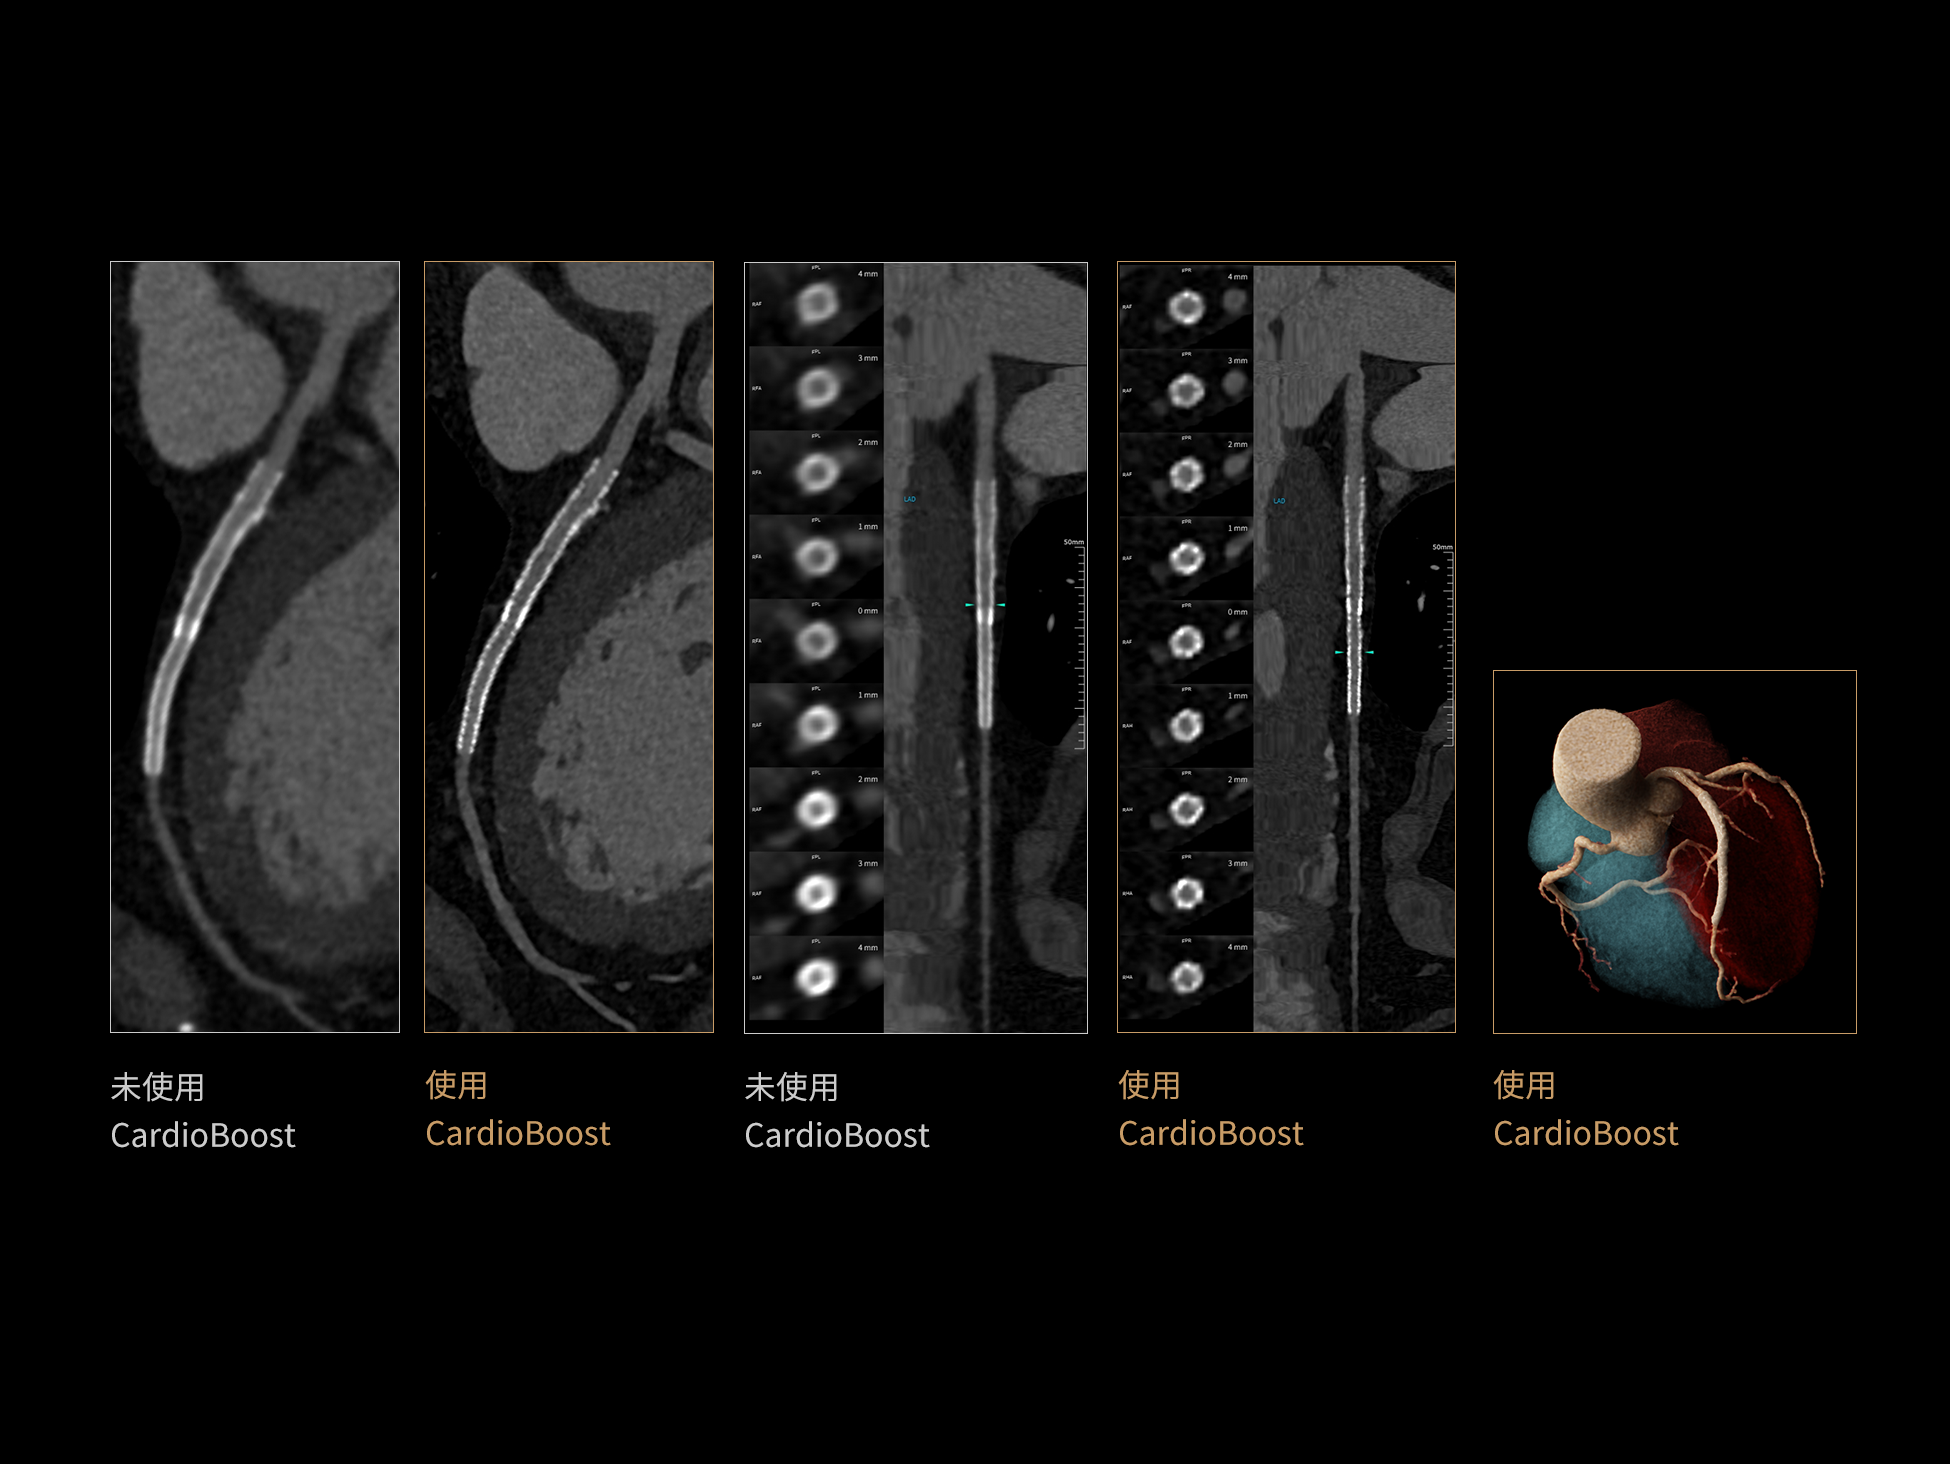

CardioBoost:专属网络设计,重塑心脏影像表现

目前心脏的 CT 检查还存在辐射剂量偏高、空间分辨率不足、 致密钙化伪影影响冠脉狭窄程度评估等方面的限 制[1][2]。CardioBoost 技术专为心脏 CT 高清成像而开发,通过 3D 神经网络的深度学习技术,利用先进的注意力机制在识别关键成像特征方面的出色表现,能够精确地聚焦于斑块、支架以及微小血管等关键细节,清晰展示这些结构与冠脉血管的边界,从而显著提高诊断的准确性,并提升医生的诊断信心。创新的 CardioBoost 心脏图像重建算法,不仅实现了图像清晰度的提升和伪影的去除,更能在减少辐射剂量的同时,保证心脏图像的高质量和图像纹理的自然。

CardioBoost核心创新

采用 3D 神经网络的空间结构优势与精细的组织分类能力,CardioBoost 技术优化了组织对比,高清展示血管斑块,使斑块与血管边缘的轮廓清晰可辨,提升斑块诊断与评估的精确性。

借助 3D 神经网络设计、空间注意力机制聚焦与特征强化作用,CardioBoost技术提升图像的空间分辨率,实现冠脉支架的高清成像,对支架形态与管腔通畅度的评估更精准。

CardioBoost 整合先进的 3D 神经网络和空间注意力机制,大幅增强数据处理的速度与精确度。该技术能有效抑制由致密钙化引起的晕状伪影,清晰展现钙化斑块的原始结构和大小,对冠脉狭窄的评估更加精确可靠。

对比度强化模块

分辨率强化模块

伪影抑制模块